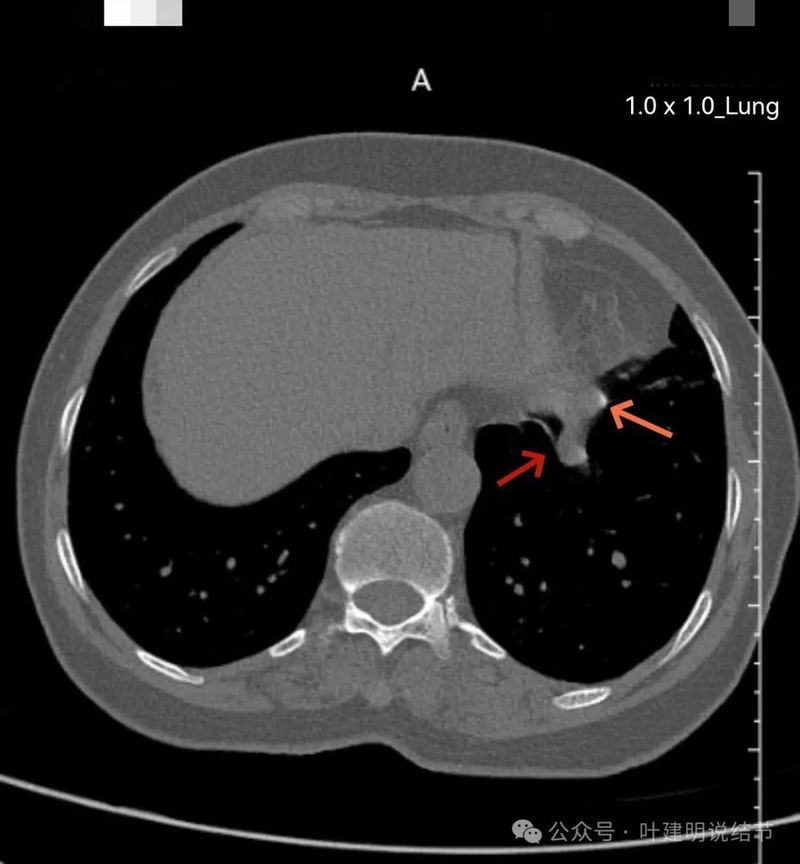

与膈肌之间间隙明显,病灶实性,膨胀性明显,边缘相对较为光滑。

整体感觉较圆,膨胀性是明显的。膈肌有点被它顶过去的样子。

纵隔窗见病灶实性密度,与膈肌间有低密度线状间隙。

病灶密度稍不均。

较为边缘部分的纵隔窗样子。